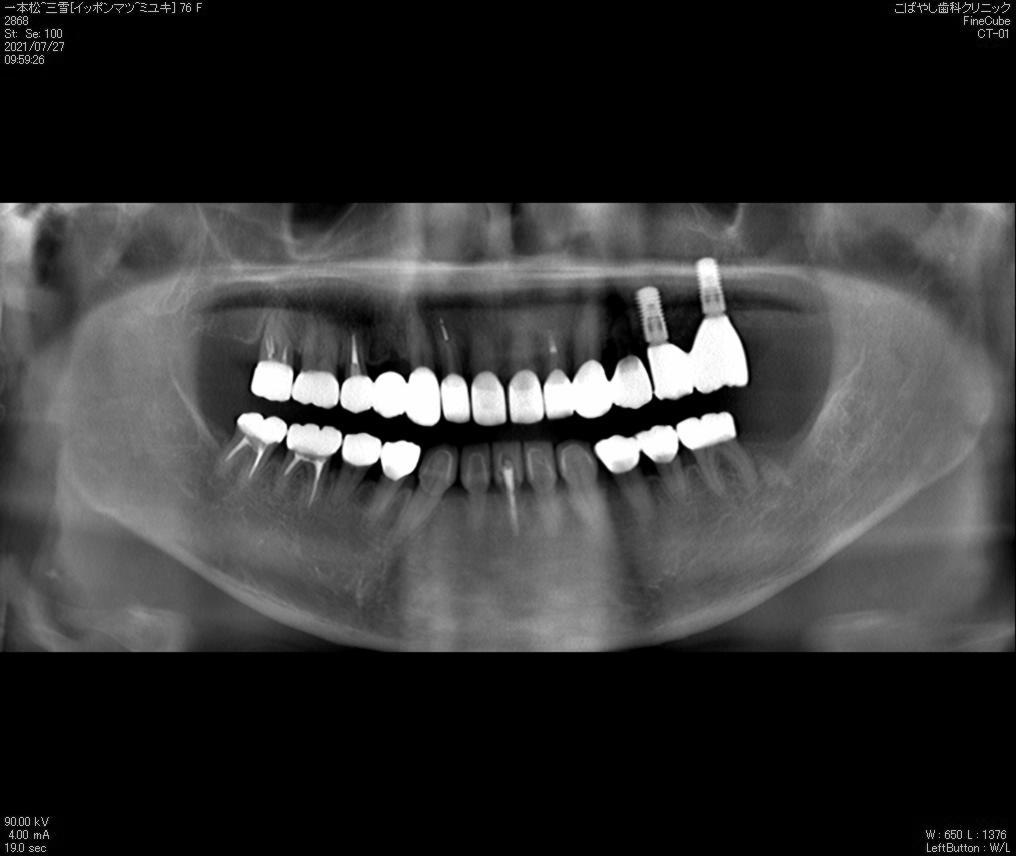

レントゲン検査

レントゲン

歯周病の進行にともない、歯槽骨が溶けていきます。レントゲンによって歯槽骨の状態を検査し、症状の進行段階を確認します。

治療前レントゲン

治療後レントゲン